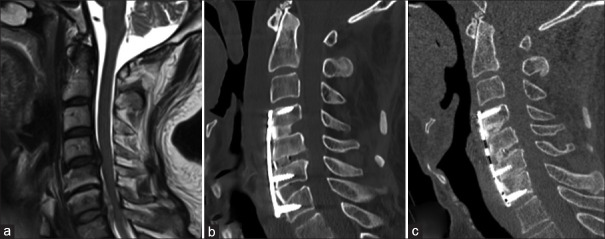

Methods: Fifty-two patients who underwent management of NCDDD and two-level contigious disc disease (CDD) over 6 years from 2014 to 2020 were included in the study. There were 44 male and 8 female patients with a mean age of 46.75 years. These patients were divided into two groups: Those who underwent contiguous discectomy and those who underwent skip discectomy with either anterior cervical discectomy (ACD) alone, ACD and fusion (ACDF), or ACDF with plating based on individual pathology and surgeon preference. Outcomes were assessed using clinical parameters such as modified Japanese Orthopaedic Association Score (mJOAS) and Nurick grade and radiological parameters such as disc height improvement, spinal alignment change, and fusion rates.

Results: The overall mean duration of follow-up was 15.23 ± 23.69 months, with a clinical follow-up period of 23.87 ± 21.51 months and a radiological follow-up period of 7.57 ± 5.91 months, with follow-up in Group 1 being 24.67 ± 23.17 months and in Group 2 being 20.03 ± 10.53 months. The mean blood loss in Group 1 was 200.47 mL; in Group 2, it was 172 mL. The preoperative mJOAS was 10.19 ± 3.16, and the postoperative mJOAS was 12.73 ± 2.92 (P = 0.001). Nurick grade showed improvement from a preoperative mean score of 4.23 ± 1.02-3.65 ± 0.88 postoperatively (P < 0.001). Statistically significant improvement in intervertebral height at superior and inferior levels was observed. Outcomes for Skip discectomy regarding mJOAS, Nurick grade, radiological parameters, fusion, and complication rates were noninferior to contiguous discectomy and fusion.

Conclusion: Skip discectomy has a similar benefit and risk profile and is noninferior compared to contiguous discectomy in addition to the preservation of intermediate disc integrity.